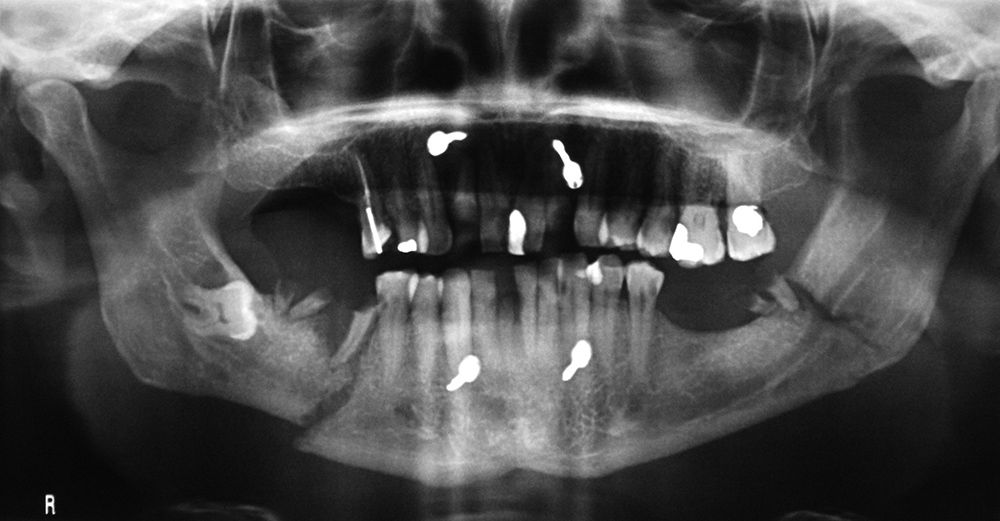

Mixed dentition in a child with permanent teeth plus retained primary teeth. The + marks developmental follicles for the third molar and the * marks permanent second molars. |